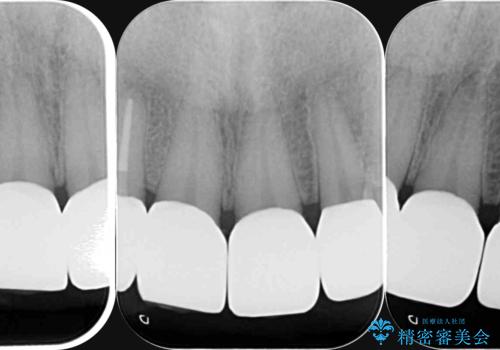

「 放置した虫歯 」 前歯セラミック治療

- 前歯の虫歯に気付きながらも放置し、一念発起し治療を希望され来院されました。

虫歯のマイクロスコープによる丁寧な除去、根管治療、深い虫歯に対する挺出(エクストリュージョン)および歯周外科を行ったのち精度の高いセラミッククラウン製作治療を計画します。

虫歯の放置により、根管治療や深い虫歯に対する処置が必要になりましたが丁寧に一つづつ処置を行ったことで抜歯をすることなく歯を残すことができました。